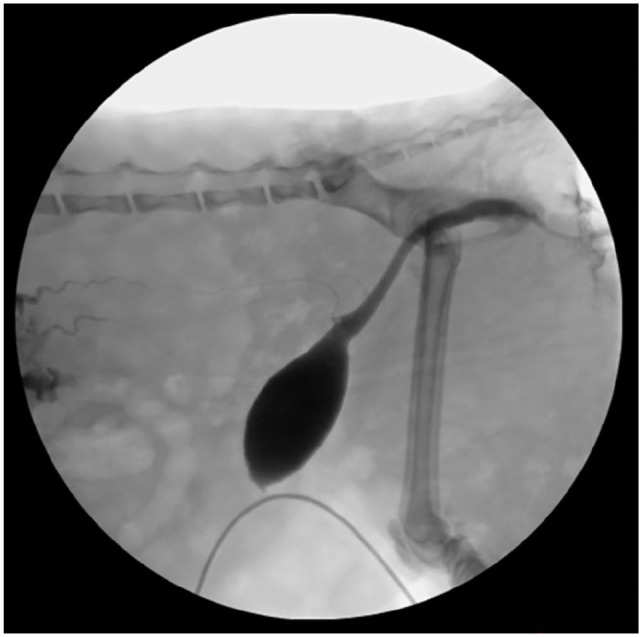

病例总结:一只8个月大的雄性家短毛猫因急性奇异尿症、大便尿症和发声而被报道。患者被诊断为尿道梗阻并住院治疗。出院后36小时,猫开始排出严重的出血性尿,并被诊断为尿腹膜和尿腹膜后。腹部超声和透视逆行阳性对比膀胱输尿管造影未发现尿路破裂的来源。剖腹探查发现双肾漏尿,伴肾盂及肾实质破裂。怀疑无菌肾盂肾炎合并肾出血导致双侧输尿管梗阻,继发尿后腹膜,延伸至尿腹膜。左侧输尿管肾切除术和右侧输尿管皮下旁路置入术作为挽救术;然而,由于预后不良,术中选择安乐死。相关性和新信息:肾盆腔和肾实质破裂是猫尿腹的一个很少报道的原因。此外,虽然严重的肾出血尚未在猫中被描述,但它可能导致双侧输尿管梗阻和尿腹。

Case summary: An 8-month-old male castrated domestic shorthair cat was presented for acute stranguria, pollakiuria and vocalization. The patient was diagnosed with urethral obstruction and hospitalized for medical management. At 36 h after discharge, the cat started passing severely hemorrhagic urine and was diagnosed with a uroperitoneum and uroretroperitoneum. An abdominal ultrasound and fluoroscopic retrograde positive contrast cystourethrogram did not identify a source of urinary tract rupture. An exploratory laparotomy revealed urine leakage from both kidneys, with evidence of rupture involving both the renal pelvis and parenchyma. It is suspected that sterile pyelonephritis and renal hemorrhage resulted in bilateral ureteral obstruction, and subsequent uroretroperitoneum, extending to cause uroperitoneum. Left ureteronephrectomy and right subcutaneous ureteral bypass placement was offered as a salvage procedure; however, euthanasia was elected intraoperatively because of a poor prognosis.